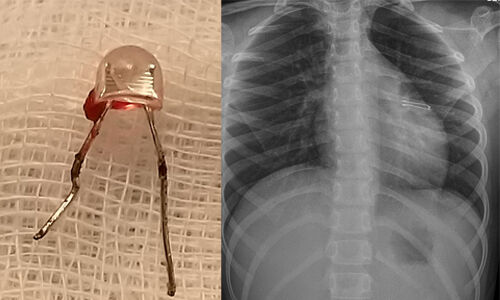

ഏഴ് വയസ്സുകാരിയുടെ ശ്വാസകോശത്തില് എല് ഇ ഡി ബള്ബ് കുടുങ്ങി ; മണിക്കൂറുകള് നീണ്ട പരിശ്രമത്തിനൊടുവില് പുറത്തെടുത്തു

കൊച്ചി: കണ്ണൂര് സ്വദേശിനിയായ ഏഴുവയസ്സുകാരിയുടെശ്വാസകോശത്തില് കുടുങ്ങിയ എല് ഇ ഡി ബള്ബ്ആലുവ രാജഗിരിആശുപത്രിയിലെ ഡോക്ടര്മാര് മണിക്കൂറൂകള് നീണ്ട് പരിശ്രമത്തിനൊടുവില് ശസ്ത്രക്രീയ കൂടാതെപുറത്തെടുത്തു. ശ്വാസകോശത്തില് എല് ഇ ഡി ബള്ബ് കുടുങ്ങിയതിനെ തുടര്ന്ന് അസ്വസ്ഥതകള് അനുഭവപ്പെട്ടകുട്ടിയെ ആദ്യം കോഴിക്കോട്ടുള്ള ഒരു സ്വകാര്യ ആശുപത്രിയില്എത്തിക്കുകയായിരുന്നു. അവിടെ വച്ച് ബ്രോങ്കോസ്കോപിയിലൂടെ ബള്ബ് പുറത്തെടുക്കാന്ശ്രമിച്ചെങ്കിലും സാധിച്ചില്ല.തുടര്ന്ന് ശസ്ത്രക്രിയ ഒഴിവാക്കുവാനും വിദഗ്ദ്ധ ചികില്സയ്ക്കുമായി കുട്ടിയെ ആലുവ രാജഗിരിആശുപത്രിയിലേക്ക് മാറ്റുകയായിരുന്നു. തുടര്ന്ന് പീഡിയാട്രിക് സര്ജറിവിഭാഗം ഡോക്ടര് അഹമ്മദ് കബീര് നടത്തിയ പരിശോധനയില് എല്ഇഡി ബള്ബ് ശ്വാസകോശത്തില് കുടുങ്ങിയതായി സ്ഥിരീകരിച്ചു.കൂര്ത്ത അഗ്രം പുറത്തേക്ക് തിരിഞ്ഞ നിലയിലാണ് ബള്ബ്ശ്വാസകോശത്തില് കുടുങ്ങി കിടന്നിരുന്നത്. എല് ഇ ഡി ബള്ബിന്റെ ആകൃതിയും കുടുങ്ങിക്കിടന്നിരുന്ന സ്ഥാനവും സാധാരണ ബ്രോങ്കോസ്കോപിയിലൂടെ അത് പുറത്തെടുക്കാനുള്ളസാധ്യത ഇല്ലാതാക്കി.

ഫൈബ്രോഒപ്റ്റിക് ബ്രോങ്കോസ്കോപിയിലൂടെ അസാധ്യമായഎല്ഇഡി ബള്ബ് പുറത്തെടുക്കല് നടപടി, താരതമ്യേനസങ്കീര്ണ്ണമായ റിജിഡ് ബ്രോങ്കോസ്കോപിയിലൂടെ ചെയ്യാന് മെഡിക്കല് സംഘം തിരുമാനിക്കുകയായിരുന്നു.കൂര്ത്ത അഗ്രങ്ങളുള്ള എല് ഇ ഡി ബള്ബ് ശ്വാസകോശത്തില് മുറിവുകള് ഏല്പ്പിക്കാതെയും രക്തസ്രാവം ഉണ്ടാക്കാതെയും സുരക്ഷിതമായി പുറത്തെടുക്കുക എന്നത് ഒരുവെല്ലുവിളിയായിരുന്നു. അടിയന്തിര സാഹചര്യം ഉണ്ടായാല് ശസ്ത്രക്രിയയ്ക്കായി തൊറാസിക് സര്ജറി വിഭാഗവും സജ്ജമായിരുന്നു.രണ്ട് മണിക്കൂര് നീണ്ടുനിന്ന പരിശ്രമത്തിനൊടുവില് ഡോക്ടര്മാരുടെ സംഘം റിജിഡ് ബ്രോങ്കോസ്കോപിയിലൂടെഎല് ഇ ഡി ബള്ബ് പുറത്തെടുത്തു.